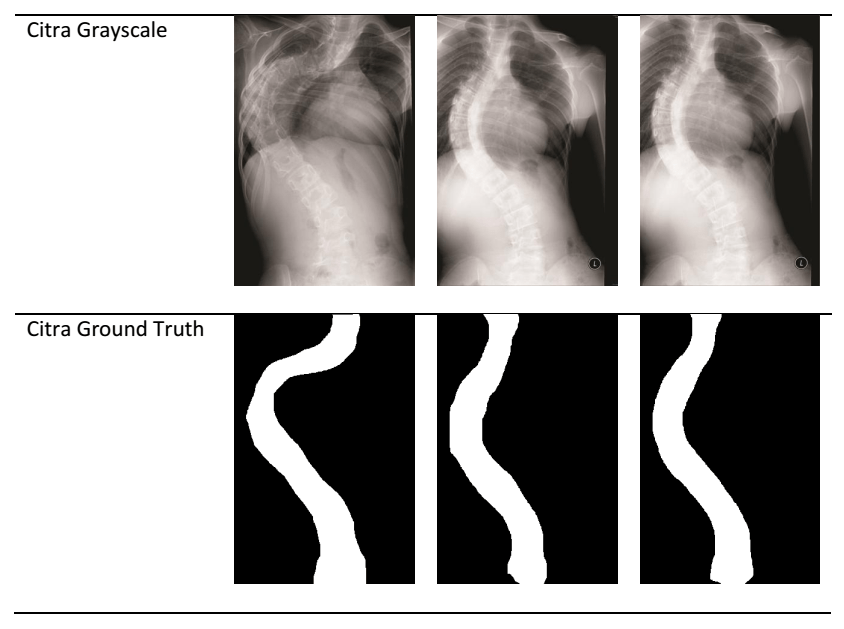

Dalam percobaan ini digunakan 15 citra rontgen berformat grayscale, masing-masing memiliki citra ground truth biner yang menandai area tulang belakang. Semua citra diubah ukurannya menjadi 450×300 piksel agar konsisten untuk pelatihan.

Gambar di atas memperlihatkan:

- Kiri: Citra rontgen asli

- Tengah: Hasil segmentasi biner

- Kanan: Citra ground truth